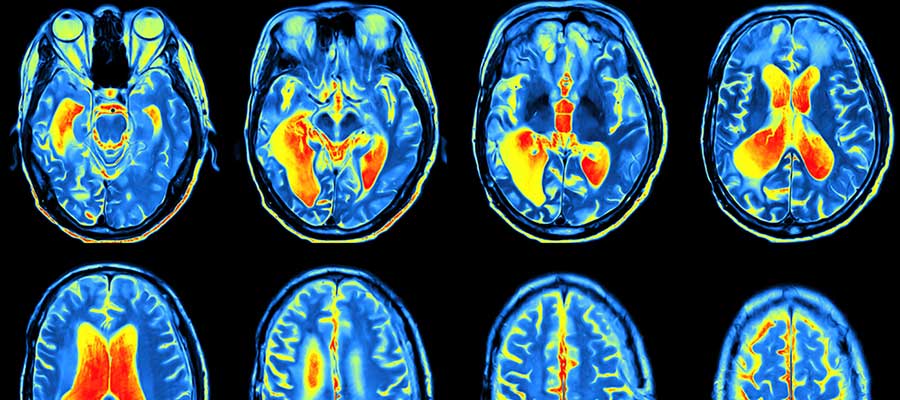

Magnetic Resonance Imaging (MRI) is actually a medical imaging way that is utilized in radiology within the formation of physiological and anatomic body processes. MRI scanners employ radio waves, magnetic field gradients and robust magnetic fields to produce body organ images. That is why, a licensed MRI technologist is needed to capture the photos the doctor needs.